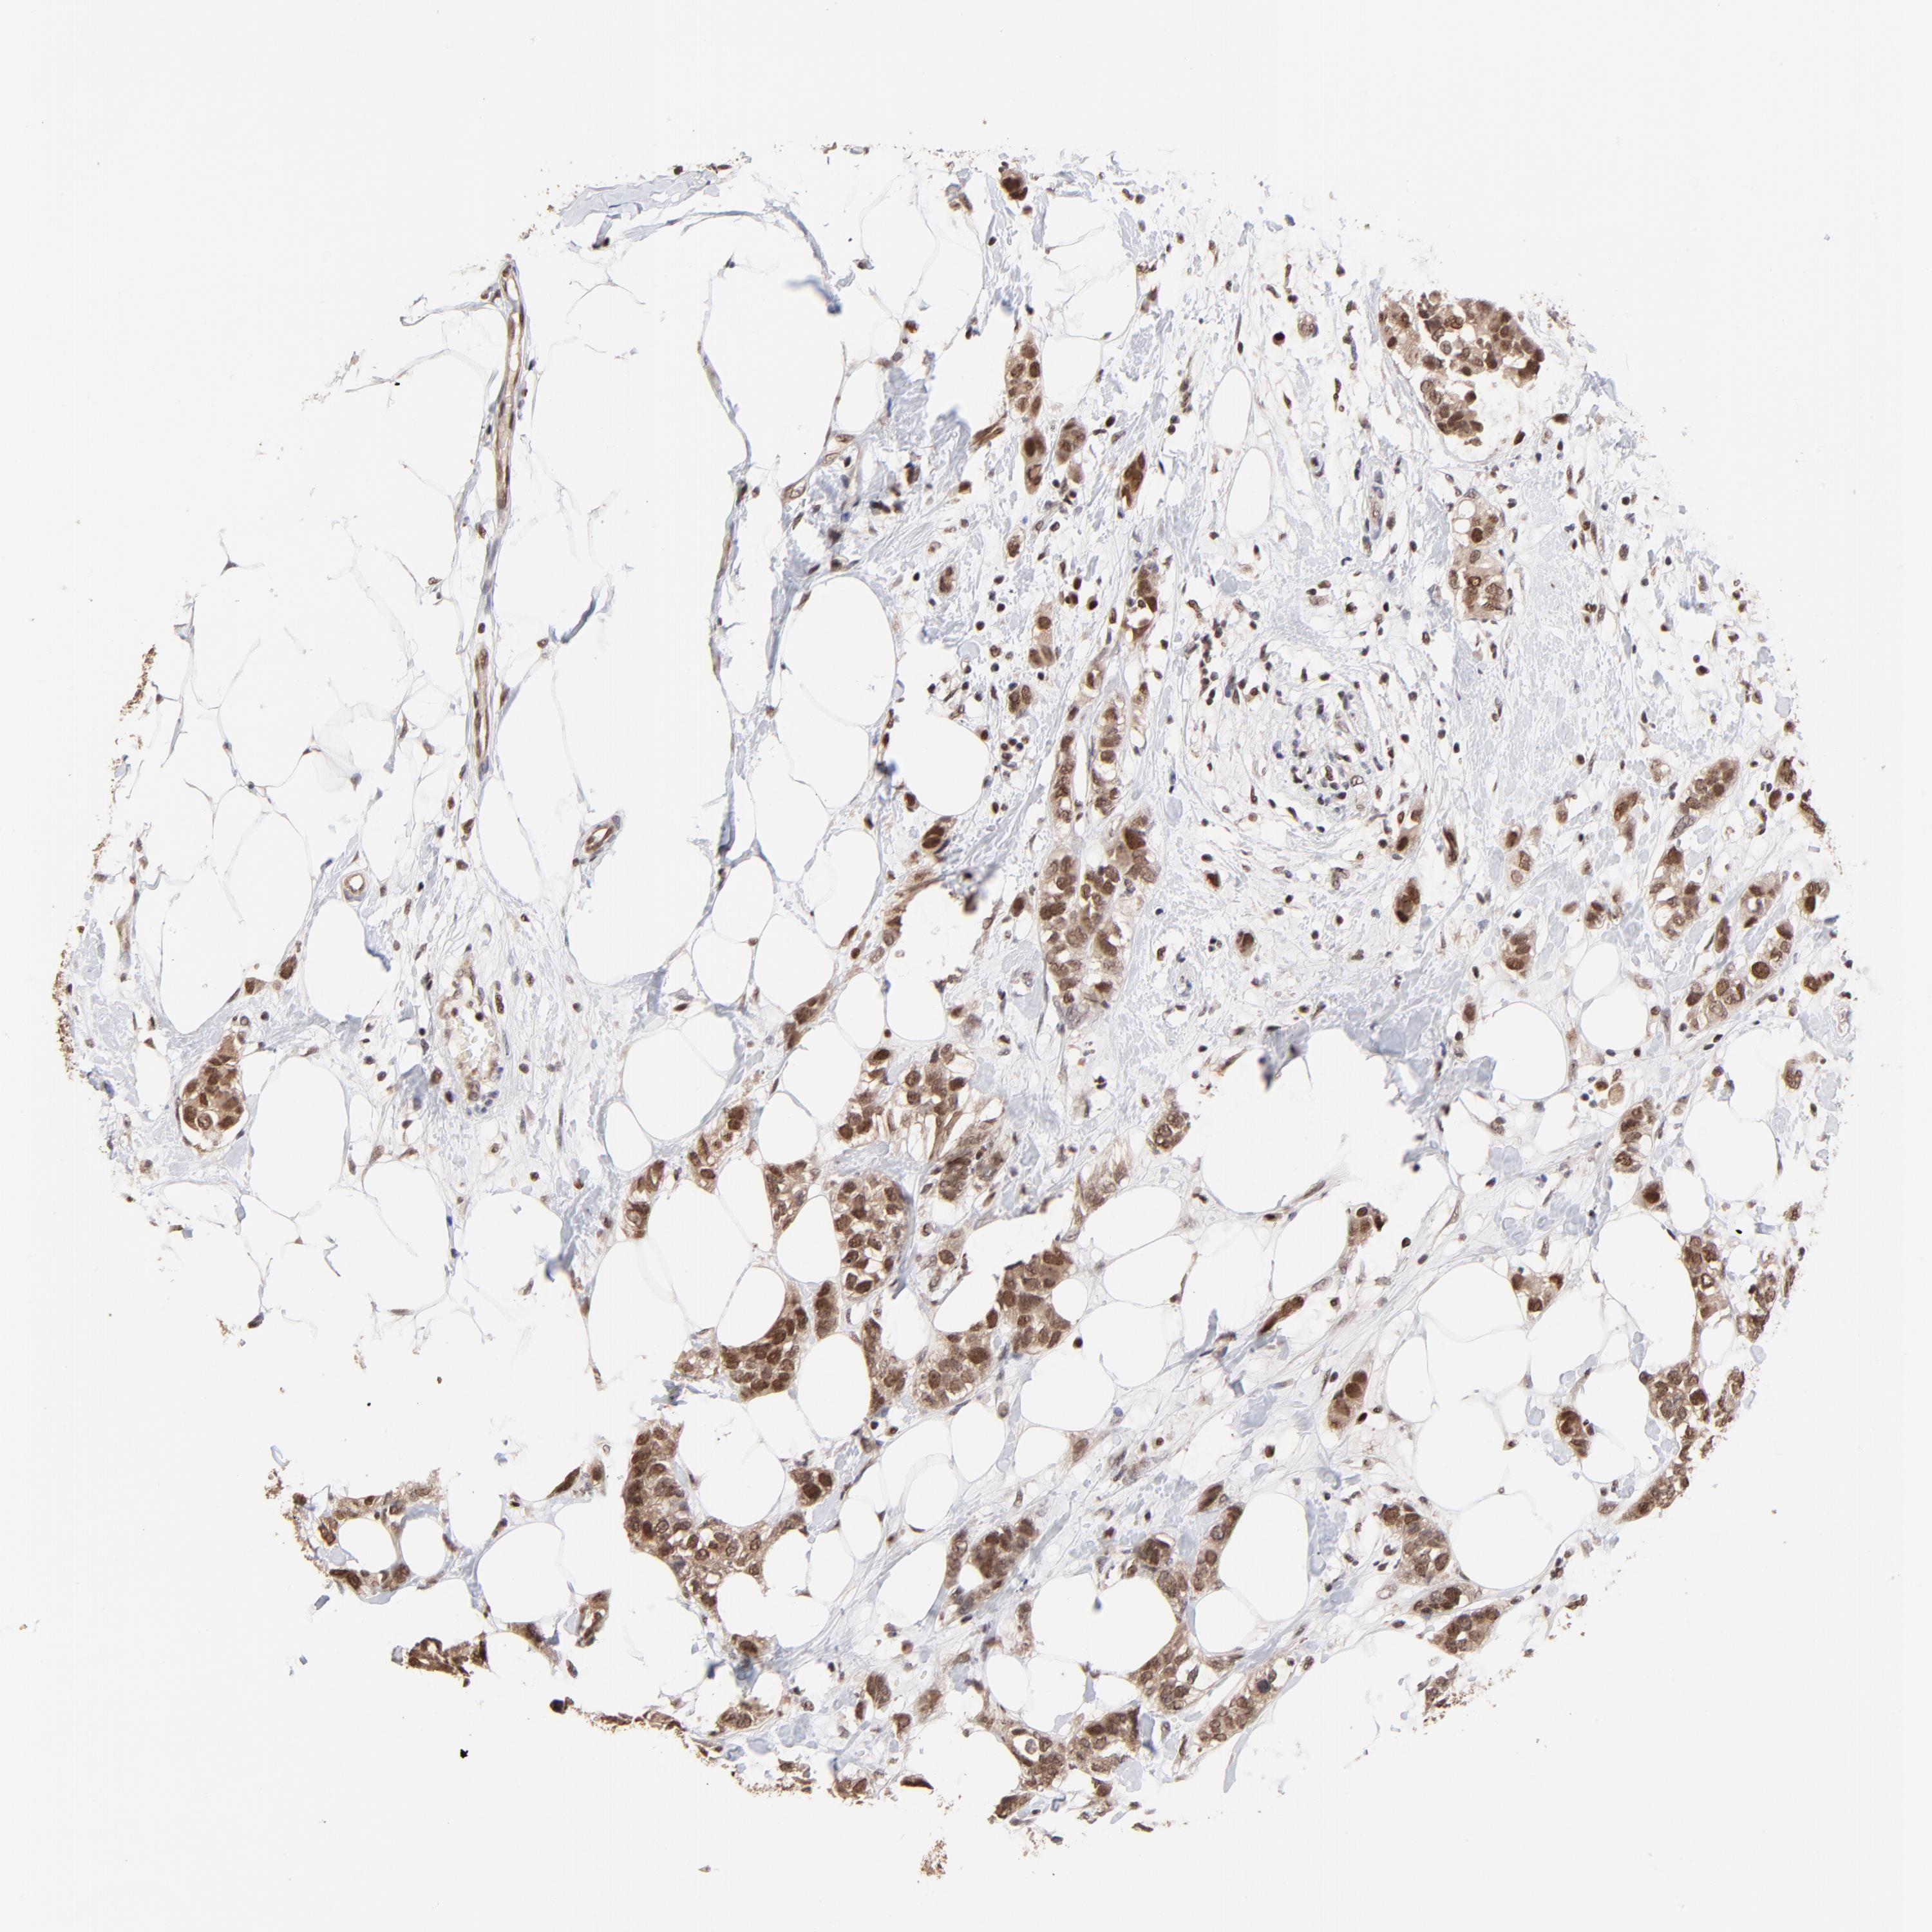

CANCER BREAST CANCER Show tissue menu

BRCA TCGA BRCA VALIDATION PROTEIN EXPRESSION

ANTIBODIES

AND

VALIDATION